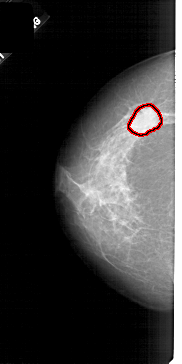

A_1820_1.LEFT_CC

LEFT_CC LINES 5086 PIXELS_PER_LINE 2536 BITS_PER_PIXEL 12 RESOLUTION 43.5 OVERLAY

FILE: A_1820_1.LEFT_CC.OVERLAY

TOTAL_ABNORMALITIES 1

ABNORMALITY 1

LESION_TYPE MASS SHAPE OVAL MARGINS ILL_DEFINED

ASSESSMENT 4

SUBTLETY 4

PATHOLOGY MALIGNANT

TOTAL_OUTLINES 1

BOUNDARY